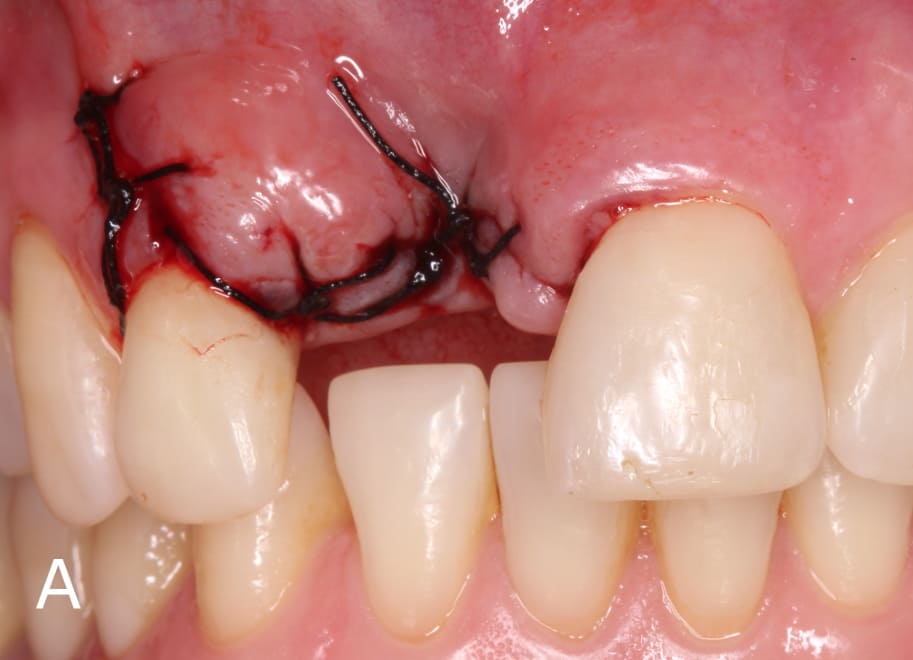

Después de la extracción del elemento dentario (Figura 1), se realizó una preparación palatina en esmalte para adaptar la fibra de vidrio (Interlig, Angelus Industria de Productos Odontológicos S/A, Paraná, Brasil) con resina compuesta sin interferir con la oclusión, ya que las fibras de vidrio deben cubrirse com resina compuesta y nunca deben exponerse al medio bucal.

Se posicionó la fibra de vidrio en las preparaciones de los dientes 21 y 12 (Figura 5), se cubrió el área com resina y se fotopolimerizó por 20 segundos (Figura 6). Luego, el diente de stock se colocó sobre la fibra trenzada y se unió a ella con resina compuesta (Figura 7). Después de posicionar la confección de la prótesis adhesiva, se realizó el ajuste oclusal necesario respetando los fundamentos de una oclusión estable bilateral.